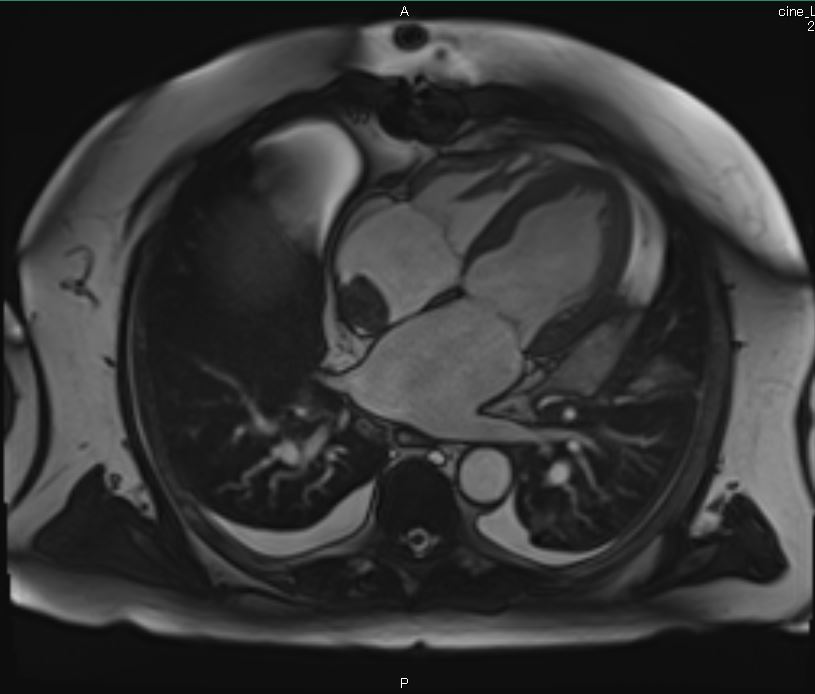

Cardiac MRI was performed on January 3, 2018, which revealed a large 2.5 × 2.9-cm lobular, fairly sessile mass in the right atrium. Without evidence of tissue destruction to suggest a malignant process, the lesion was suggestive of either myxoma or hematoma due to marked contrast uptake (which is seen less often with myxomas) (Figure 1).

Figures 1A-G. Cardiac MRI findings of a large, lobular, fairly sessile mass in the right atrium, measuring 2.5 x 2.9 cm, suggestive of either myxoma or hemangioma.